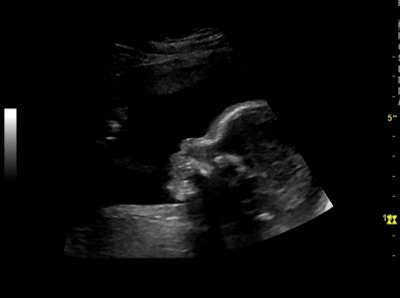

Ultraschallbilder Schwangerschaft